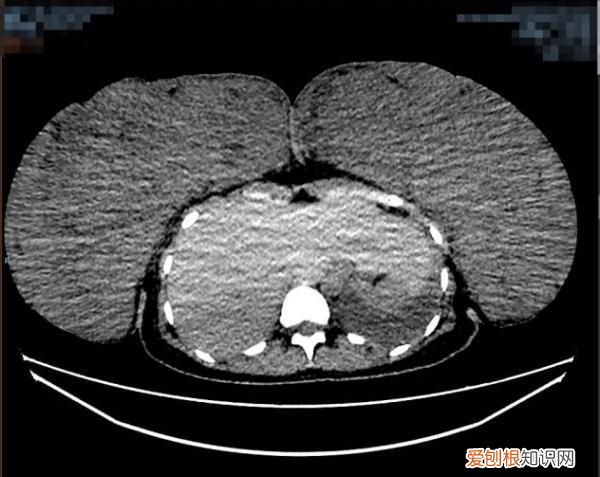

该患者胸部增强CT术前(左图)术后(右图)对比图,其中术前大小约:267mm×100mm×293mm(左),125mm×270mm×340mm(右)